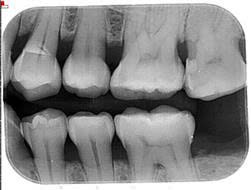

XQuang trước – sau điều trị

Việc quan sát đúng cách có thể giúp loại bỏ sâu răng đầy đủ. Ba điều kiện thiết yếu cần đạt được trong quá trình phẫu thuật để có thể quan sát đúng cách nhằm ngăn ngừa việc loại bỏ men răng/ngà răng không đủ trong quá trình chuẩn bị khoang: (i) trường phẫu thuật thông thoáng, (ii) kiểm soát độ ẩm chặt chẽ và (iii) độ phóng đại phù hợp. Cần có trường phẫu thuật thông thoáng trước khi can thiệp phẫu thuật. Loại bỏ mảng bám, mảnh vụn và cao răng trên/dưới nướu là điều cần thiết. Ngoài ra, để đảm bảo tổn thương có lỗ rỗng và cải thiện khả năng tiếp cận bằng thị giác, việc tách răng bằng cách đặt một dụng cụ tách đàn hồi chỉnh nha trong một tuần để tạo ra một khoảng cách nhỏ ở kẽ răng là rất hữu ích. Kiểm soát độ ẩm thông qua việc sử dụng đê cao su rất hữu ích cho việc phục hồi chất lượng cao. Ngoài ra, sử dụng kính lúp phóng đại giúp giảm tình trạng nhô ra ở rìa răng tới 40%. Tình trạng nhô ra có thể ảnh hưởng đến việc đánh giá kết quả lâm sàng của phục hồi trong các lần tái khám do gây ra sự hiểu sai về lý do thất bại. Thất bại của phục hồi có thể là do nhô ra và rò rỉ thay vì do chính đường hầm. Các phương pháp tiếp cận trái ngược khác để tạo điều kiện loại bỏ sâu răng đầy đủ bao gồm tăng kích thước của đường tiếp cận nhai và áp dụng kiểm tra chụp X quang. Tuy nhiên, việc tăng kích thước của quá trình chuẩn bị đường hầm sẽ làm giảm khả năng chống gãy của răng. Một nghiên cứu đã báo cáo rằng ngay cả việc kiểm tra chụp X quang tại chỗ trong quá trình chuẩn bị đường hầm cũng không thể làm tăng hiệu quả của việc loại bỏ sâu răng. Người ta cho rằng không nên coi chụp X-quang là công cụ chẩn đoán phù hợp để xác định sâu răng trong quá trình chuẩn bị đường hầm.